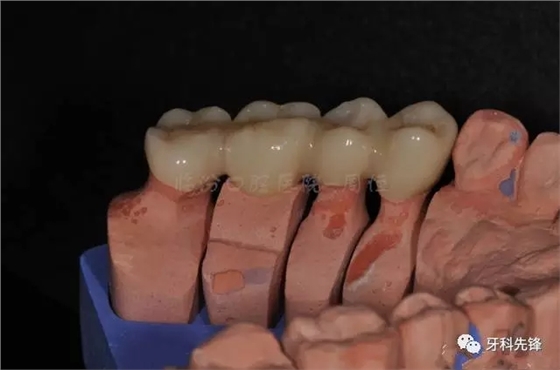

圖13牙體預(yù)備模型照